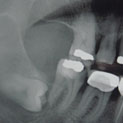

Aunque su estirpe anatomopatológica sea benigna, son quistes que en algunos pacientes provocan grandes destrucciones maxilares, porque crecen de forma asintomática durante años.

Su cirugía es sencilla y está basada en la extracción del quiste con criterios conservadores, y en la reconstrucción del defecto creado por la limpieza quirúrgica.

Para la reconstrucción, aconsejamos hacerlo en la misma intervención y con las bases de ingeniería tisular de la regeneración ósea guiada. Utilizamos como material óseo inductor el fosfato tricálcico tipo beta, mezclado con sangre del paciente y protegido con membrana de regeneración reabsorbible.